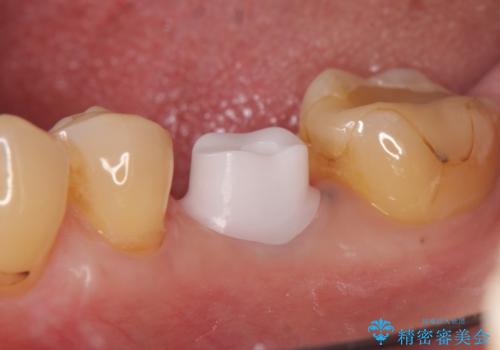

- 左下6の歯で咬むと痛みがあり、たまに膿も出てくるので診て欲しいといらっしゃった方の症例です。

被せ物を外したところ歯が割れており保存不可能だったため抜歯し、インプラントによる欠損補綴を行いました。